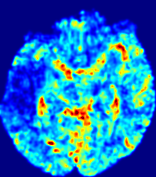

LesionRefer to captionRefer to captionRefer to captionRefer to captionRefer to captionRefer to caption𝐕rgbsubscript𝐕𝑟𝑔𝑏{\bf{V}}_{rgb}Refer to captionRefer to captionRefer to captionRefer to captionRefer to captionRefer to caption𝐕2subscriptnorm𝐕2{\|\bf{V}}\|_{2}Refer to captionRefer to captionRefer to captionRefer to captionRefer to captionRefer to captionRefer to caption3.53.53.52.82.82.82.12.12.11.41.41.40.70.70.70.00.00.0(mm/s)𝑚𝑚𝑠(mm/s)D𝐷DRefer to captionRefer to captionRefer to captionRefer to captionRefer to captionRefer to captionRefer to caption0.0200.0200.0200.0160.0160.0160.0120.0120.0120.0080.0080.0080.0040.0040.0040.0000.0000.000(mm2/s)𝑚superscript𝑚2𝑠(mm^{2}/s)Slice #1Slice #2Slice #3Slice #4Slice #5Slice #6

Figure 4: PIANO feature maps for another patient in the ISLES 2017 training set, where the lesion is located in the right hemisphere. Top row: segmented stroke lesion region (white) on different slices. The corresponding slices for the PIANO feature maps are shown in the following rows.

For a better insight into an estimated velocity field 𝐕𝐕{\bf{V}} and diffusion field 𝐃𝐃{\bf{D}}, we compute the following maps: (1) 𝐕rgbsubscript𝐕𝑟𝑔𝑏{\bf{V}}_{rgb}: Color-coded orientation map of 𝐕=(Vx,Vy,Vz)T𝐕superscriptsuperscript𝑉𝑥superscript𝑉𝑦superscript𝑉𝑧𝑇{\bf{V}}=(V^{x},V^{y},V^{z})^{T}, obtained by normalizing 𝐕𝐕{\bf{V}} to unit length and mapping its 3 components to red, green, blue respectively; (2) 𝐕2subscriptnorm𝐕2\|{\bf{V}}\|_{2}: 222 norm of 𝐕𝐕{\bf{V}}; (3) D𝐷D: scalar field in Eq. 5.

Fig. 3 and Fig. 4 show the PIANO feature maps estimated from two ISLES 2017 patients: all are highly consistent with the lesion in both cases. Details of the blood flow trajectories are revealed in 𝐕rgbsubscript𝐕𝑟𝑔𝑏{\bf{V}}_{rgb} by the ridged patterns and the sharp changes of colors in the unaffected (right) hemisphere, while the flat patterns appearing within the lesion provide little directional information about the velocity and indicate low velocity magnitudes. Velocity magnitudes are more directly visualized via 𝐕2subscriptnorm𝐕2\|{\bf{V}}\|_{2}, from which one can easily locate the lesion where 𝐕2subscriptnorm𝐕2\|{\bf{V}}\|_{2} is low. D𝐷D also indicates lower diffusion values in the lesion, though with less contrast potentially due to the fact that it captures the accumulated effect of CA diffusion at the voxel-level.